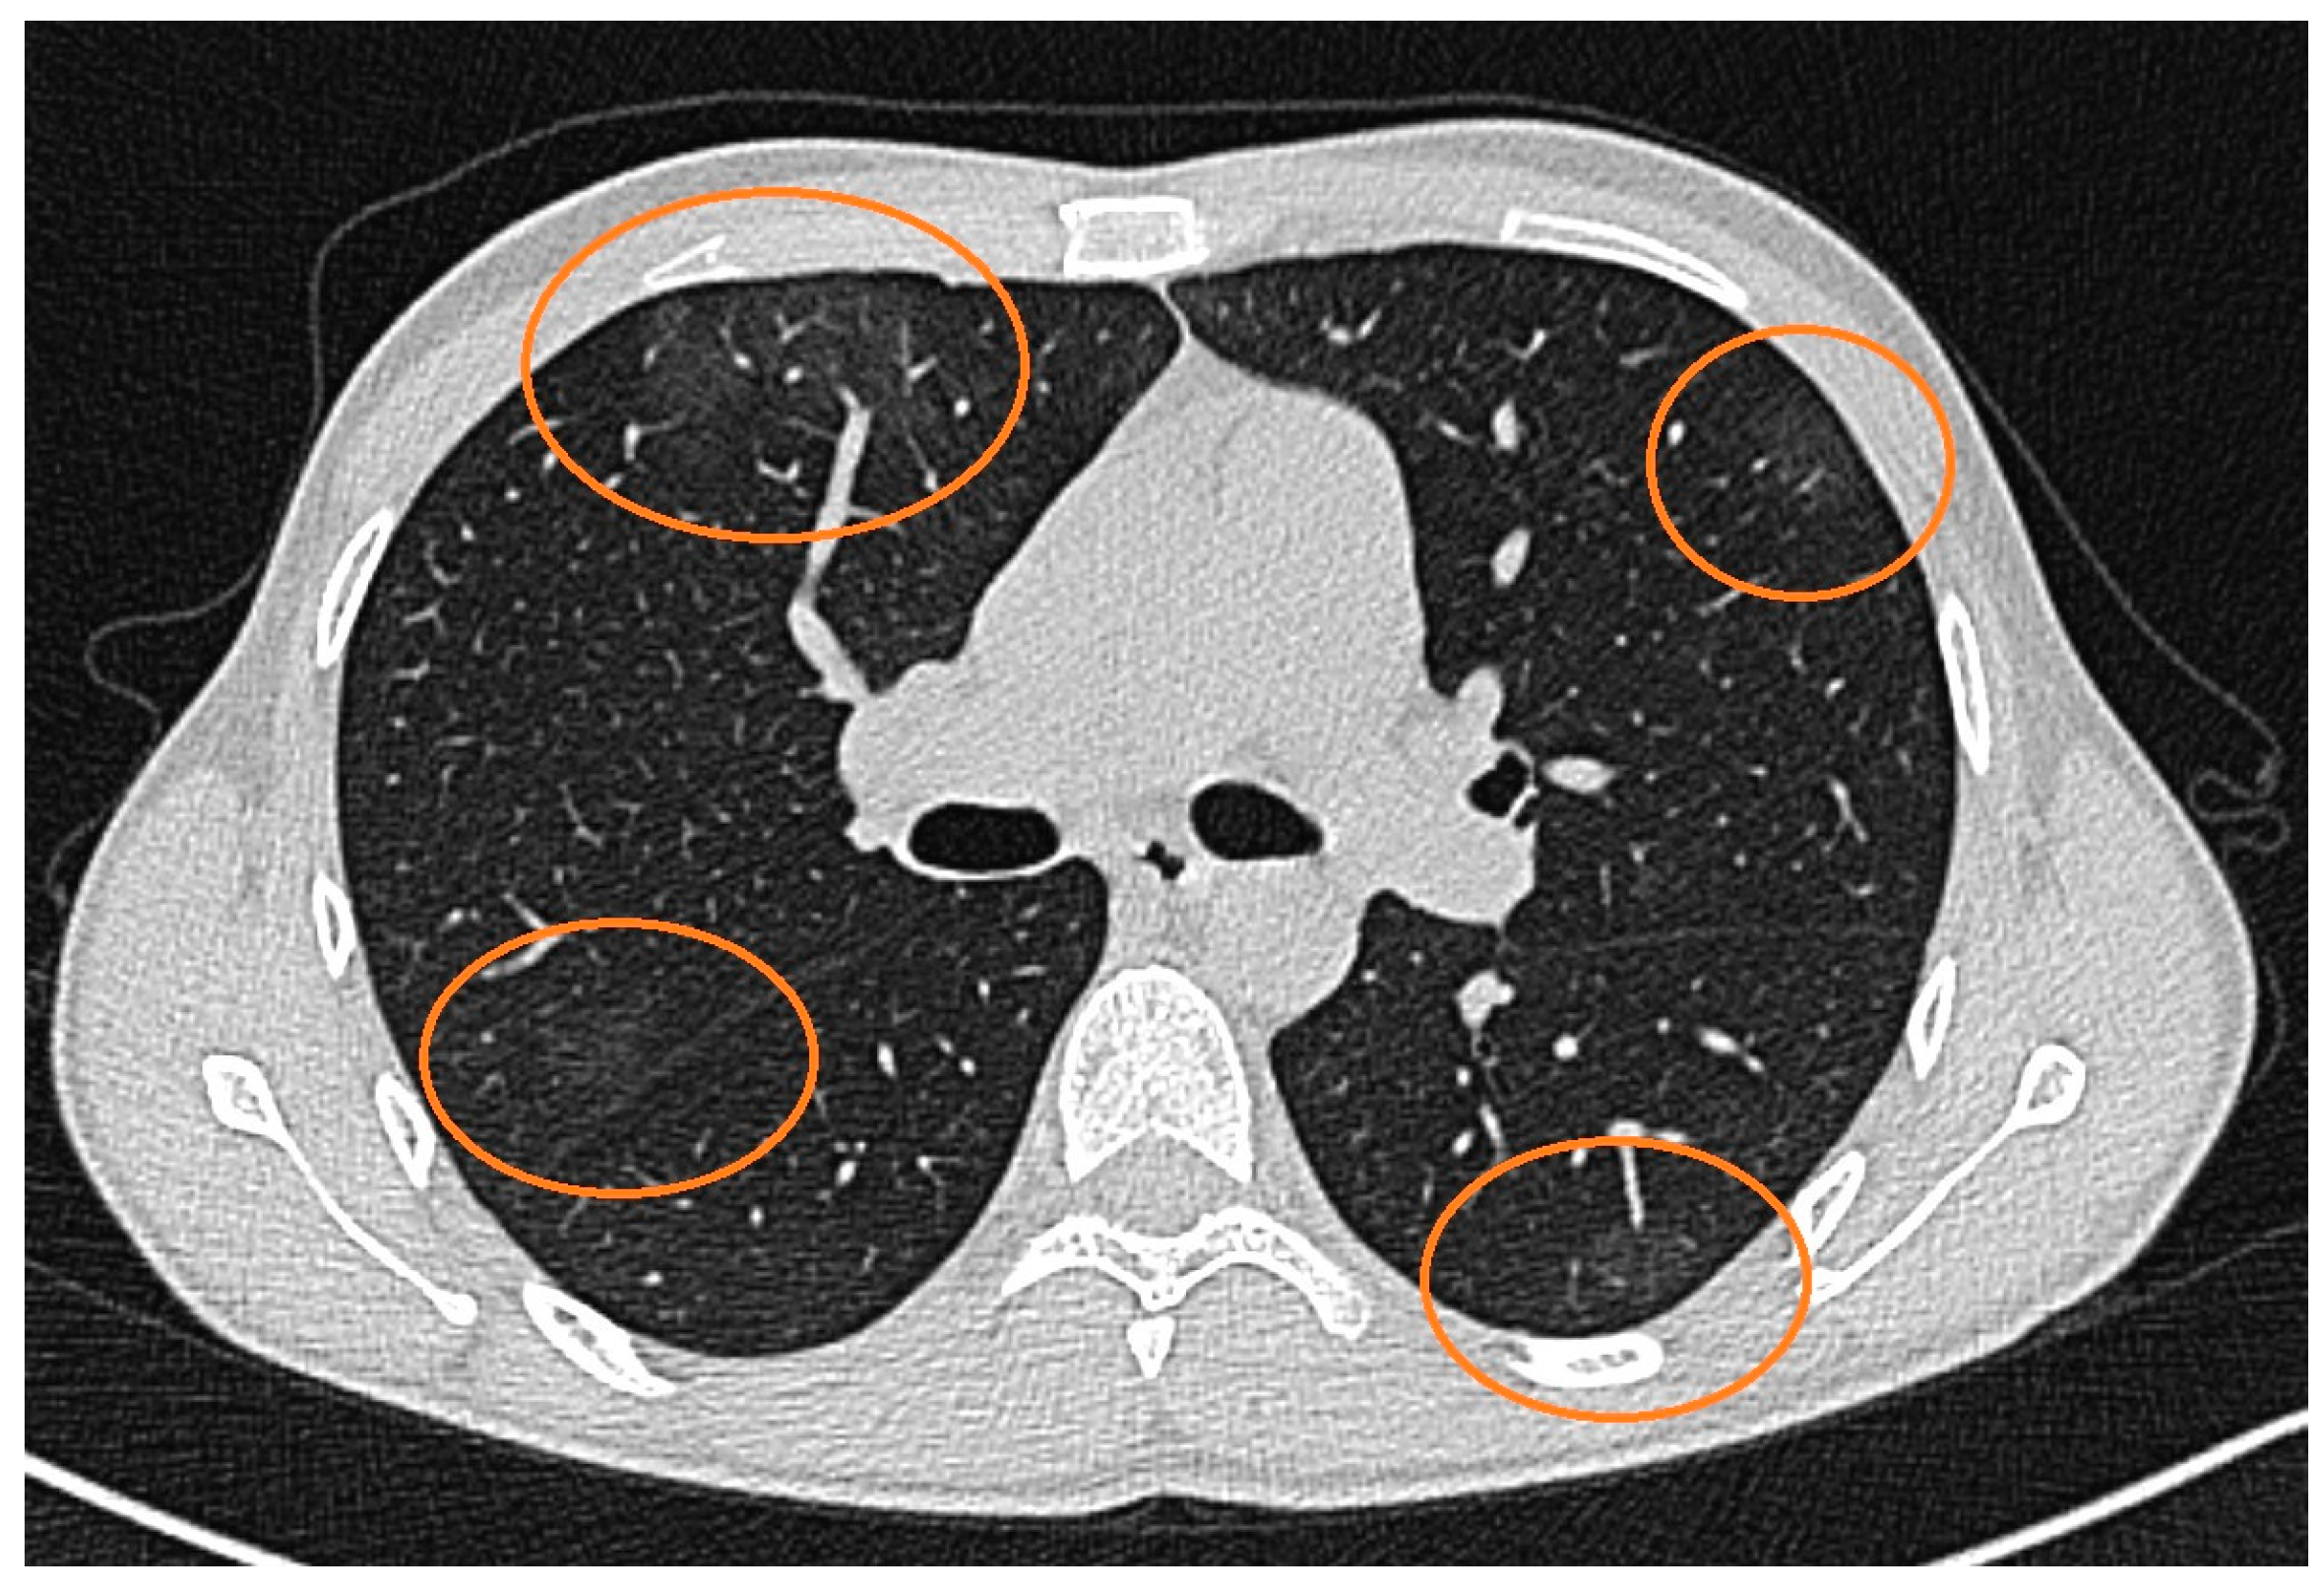

A 32-year-old Caucasian man presented at the Ophthalmology Department complaints of decreased vision and ocular pain accentuated during movement that appeared a day before. A week before the onset, the patient also had symptoms specific to a transient ischemic attack, with the loss of muscle force on the right upper limb and aphasia. On ocular examination, his vision in the right eye was 6/6 and in the left eye was HM (hand motion). Slit lamp biomicroscopy, which represent the instrument used to examine the anterior and posterior segments of the eye under high magnification, showed signs of anterior uveitis, with discrete corneal endothelial edema and micro Tyndall, in the right eye and severe corneal endothelial edema—granulomatous inferior inflammatory cells deposited on the cornea-keratic precipitates—and moderate Tyndall in the left eye. Fundus examination showed a small peripapillary infiltrated zone of white necrosis and in the extreme nasal periphery a zone of white necrosis with edema located along the distribution of retinal vessels in the right eye. In the left eye, the fundus examination showed pseudopapilledema, with hemorrhagic necrosis on white/yellow cloudy retinal lesions, centered around vasculature (Figure 1). OCT of the left eye showed necrosis of the fovea, resulting in significant destruction of the retinal nerve fiber layer.

Figure 1.

Fundus photographs of the right and left eyes. At presentation, the right eye shows small peripapillary infiltrated zone of white necrosis and the left eye shows pseudopapilledema, with hemorrhagic necrosis on white/yellow cloudy retinal lesions.